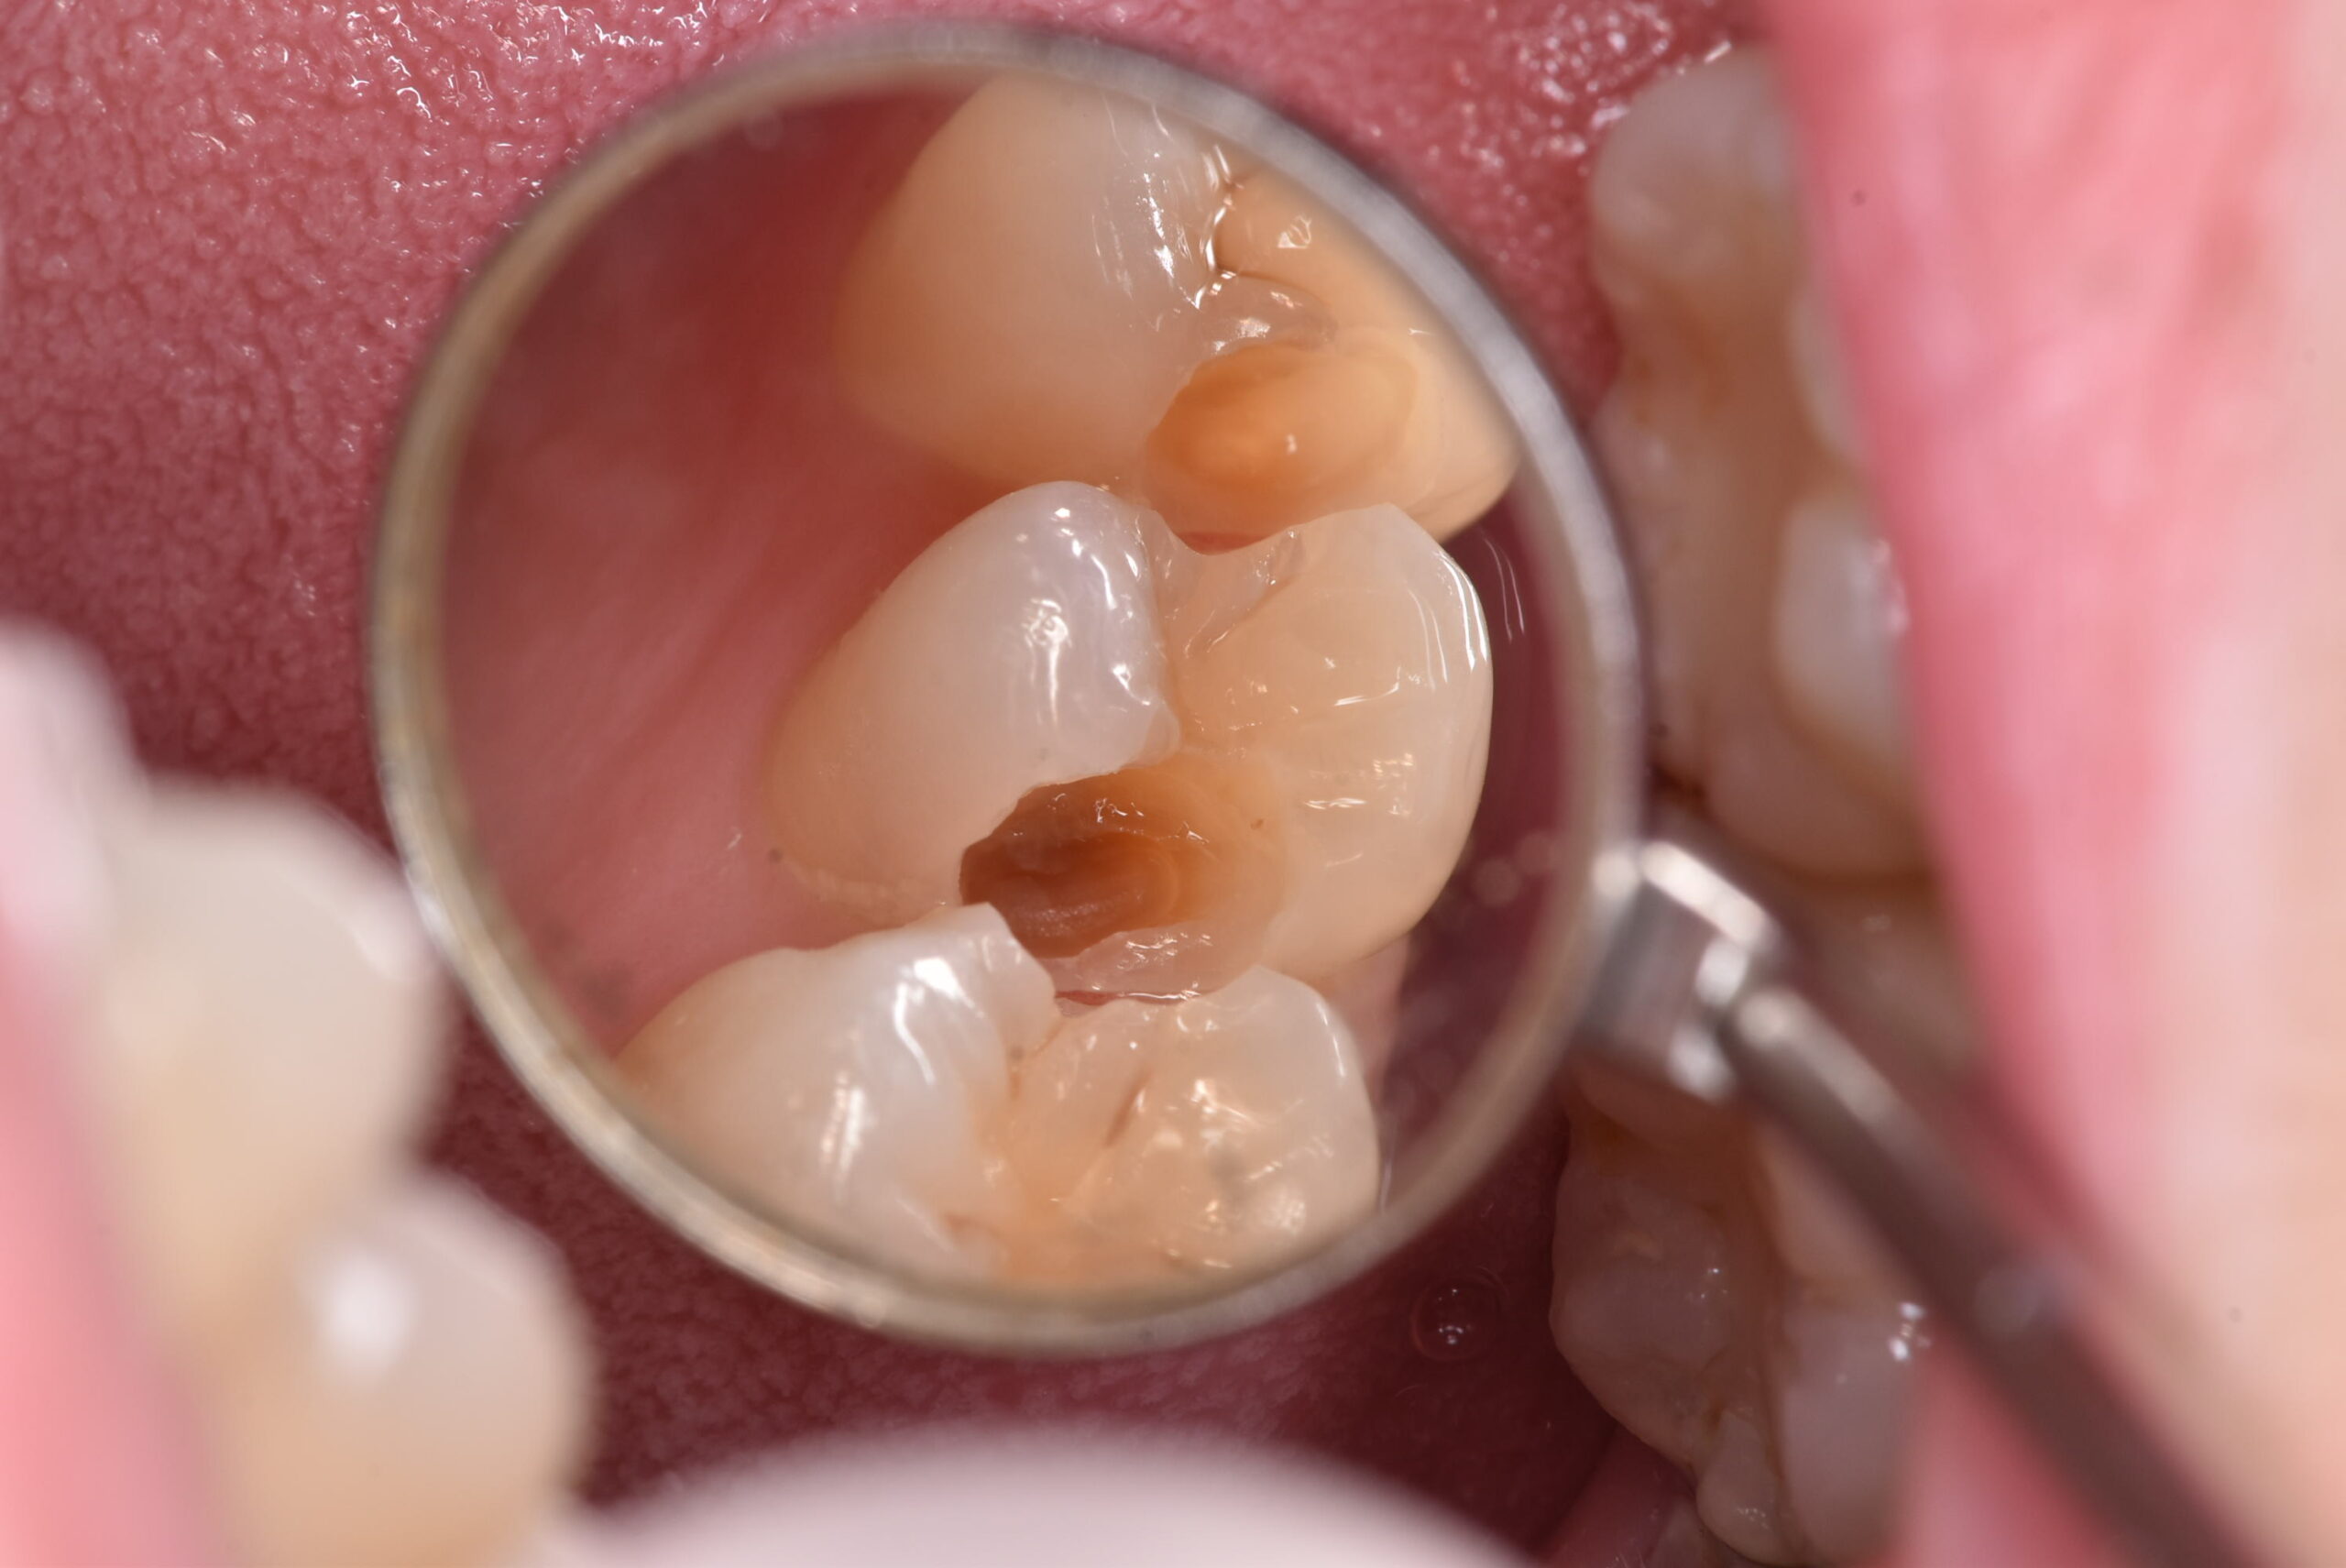

写真を見ていきましょう。実際に処置を行った時の写真です。下の写真は処置前のものになります。

間の部分にむし歯があるのですが、おわかりでしょうか?「なにもないよ!」と言う方の方が多いのではないでしょうか?では、ここを削っていったらどうなったのか、下の写真をご覧ください。

神経に到達する寸前くらいの、深いむし歯が広がっていました。これまでのブログでも書いた通り、今回も症状はありません。では、問題なかったのか?でいうと、答えは上の写真に示した通りです。